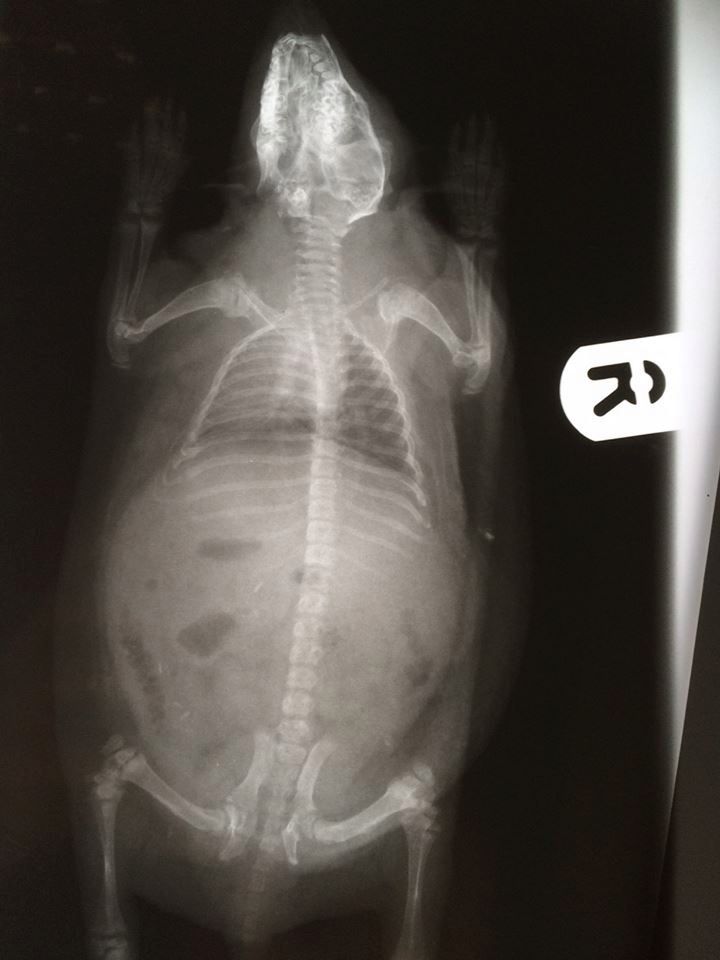

Niezwykły pacjent leczony jest w przychodni weterynaryjnej w brytyjskim Hertofdshire. Jeż Derek ma problem z łysieniem, które najprawdopodobniej jest wynikiem traumatycznego dzieciństwa.

Kiedy znaleziono go w jednym z ogrodów, był malutkim jeżykiem. Był wielkości chomika i miał na grzbiecie sporą ranę, więc weterynarze bali się się, że może zaatakować go ptak. Myśleli też, że brak kolców spowodowane jest jakąś bakterią albo pasożytem. Dopiero potem po wykonaniu szczegółowych badań okazało się, że malec łysieje.